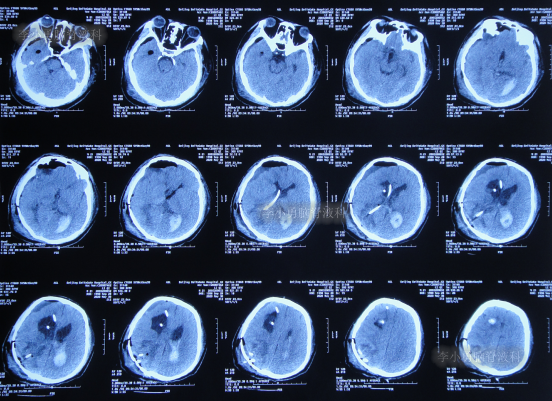

发现脑积水8年后即2013年9月16日,复查头颅CT示脑积水(图-1),没有相关症状,建议定期复查。

图-1:2013年9月16日头颅CT